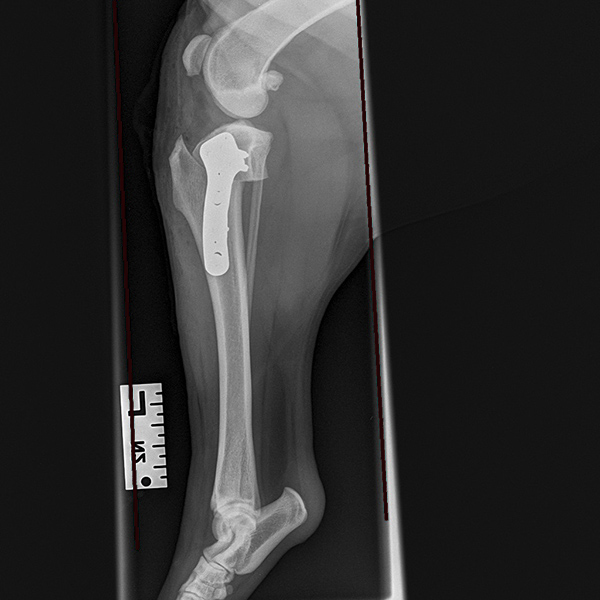

Dogs with cruciate ligament rupture often have a progressive deterioration in the use of their leg over many months. Initially, lameness is mild and transient and tends to rapidly improve with rest and anti-inflammatory medication. This mild and intermittent lameness is typical of the early stages of cruciate ligament rupture when most of the ligament is still intact and functioning. If untreated at this stage, the ligament will progressively tear, and lameness will become persistent and severe; this corresponds to a complete rupture of the ligament. TPLO surgery is the treatment of choice at any stage of cruciate ligament rupture. We recommend early treatment since this can prevent full ligament rupture from occurring, thereby hastening your pet’s recovery and improving their comfort and mobility. Drag the circle to view before and after surgery images.

TPLO surgery changes the way that the two knee bones (femur and tibia) interact through cutting, repositioning and fixing the tibia in a slightly different position. This provides joint stability without the need to replace the cruciate ligament.